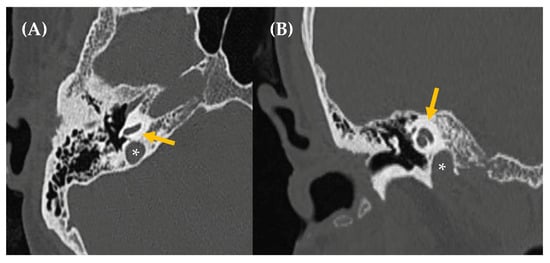

B.

High-riding/dehiscent jugular bulb

Some venous-origin PT cases may be related to a dehiscence or loss of the bony covering between a venous sinus and the mastoid air cells. In these instances, the sound of normal venous flow is excessively transmitted to the cochlea via the mastoid air cells. These dehiscences are a cause of retrotympanic vascular mass and can be identified through high-resolution temporal bone CT (Figure 7). One such case occurs when dehiscence happens at the level of the sigmoid (jugular) plate, which normally separates the jugular bulb from the hypotympanum and middle ear cavity. In other cases, the jugular bulb may be prolapsed, meaning it is located higher than usual, possibly accompanied by a dehiscence in the sigmoid plate or not. The transverse level above which a jugular bulb is considered prolapsed or high has been variably defined: when the jugular bulb apex is at the level of the floor of the IAC or 2 mm below it, if it exceeds the superior tympanic annulus, if it reaches the basal turn of the cochlea or the inferior edge of the round window niche, if it is above the floor of the external auditory canal (EAC) or inferior edge of the tympanic annulus, or if it is above the cochlear aqueduct [73]. Depending on the definition used, prevalence varies across studies, ranging from 6% to 34%. Jugular bulb ectasias or dehiscences may be treated using endovascular or surgical approaches, with careful consideration of the risk–benefit balance [71].